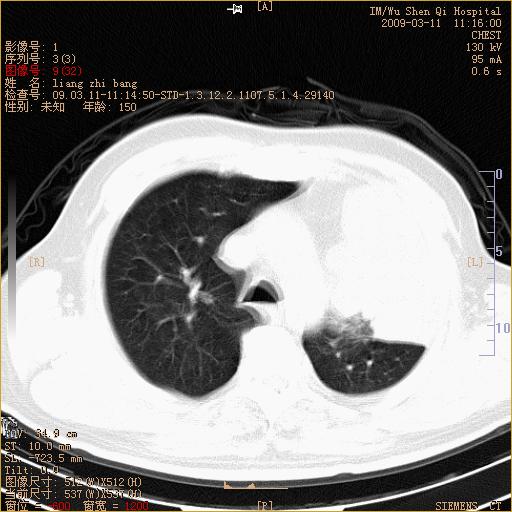

标题: CT18604:男,60岁,咳嗽一月余 [打印本页]

标题: CT18604:男,60岁,咳嗽一月余

1)考虑左肺上叶中央型肺癌并左肺上叶肺不张;建议必要时行纤支镜检查进一步明确诊断。2)左侧胸腔积液。

肺门肿块、支气管开口闭塞伴肺不张及胸水!典型的中心型肺癌变现!

1、左肺上叶中央型肺癌并上叶阻塞性肺不张。

2、左侧胸腔少量积液,右侧胸膜轻度增厚。

左肺们肿块并左肺上叶不张。考虑左肺中心性肺癌并左肺上叶不张及左侧胸腔积液